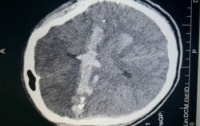

20:03 Здоровье

Украинские врачи показывают высокий профессионализм в спасении тяжёлых больных